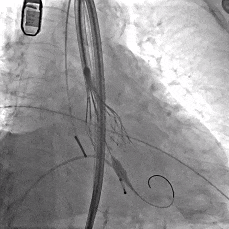

瓣膜稳定释放至全展开

造影观察

瓣膜位置可,形态佳

左冠切线观察,瓣膜位置可,冠脉灌注良好